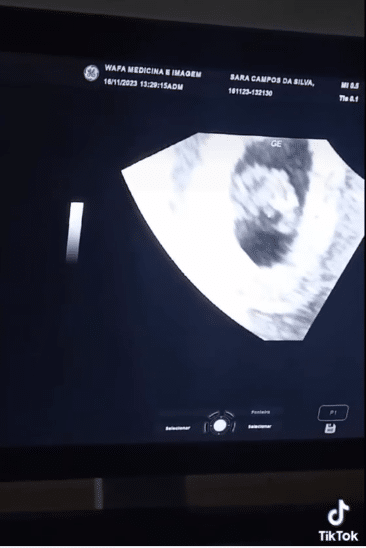

A notícia de uma gravidez costuma ser motivo de alegria, mas para Sara Campos da Silva, de 18 anos, a descoberta de que está esperando quíntuplos foi uma reviravolta emocional que a deixou com falta de ar durante o exame de ultrassom.

A jovem estudante não conseguiu conter as emoções à medida que o médico anunciava cada novo coraçãozinho. “Quando o médico falou que era um, depois dois, no terceiro eu já estava passando mal. No quinto, não o ouvi falar”, revelou Sara Campos da Silva.